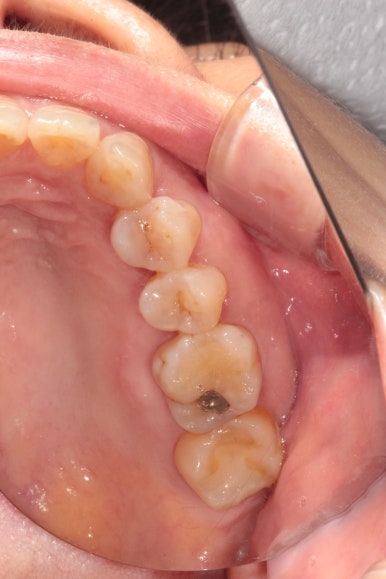

처음 시작은 충치가 있는지 풍치가 있는지 보는 것입니다.

충치검사를 꼼꼼히 해야합니다.

잇몸이 안좋으시면 잇몸치료를 먼저 완벽하게 해놓아야하고, 충치가 있으시면 충치치료를 완벽하게 해놓아야 합니다. 완벽한 잇몸치료가 생각보다 달성하기 어려운 목표인데요, 제가 또 치주과전문의 아니겠습니까? ㅎㅎ